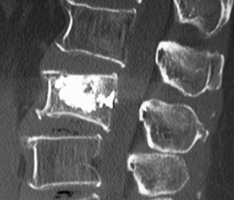

注入生物相容性的磷酸钙骨水泥的X光照片

压迫性锥体内注入骨水泥使其恢复锥体的生理形态的同时解除疼痛,防止了由于压迫性骨折导致的病理弯曲和驼背驼腰症状